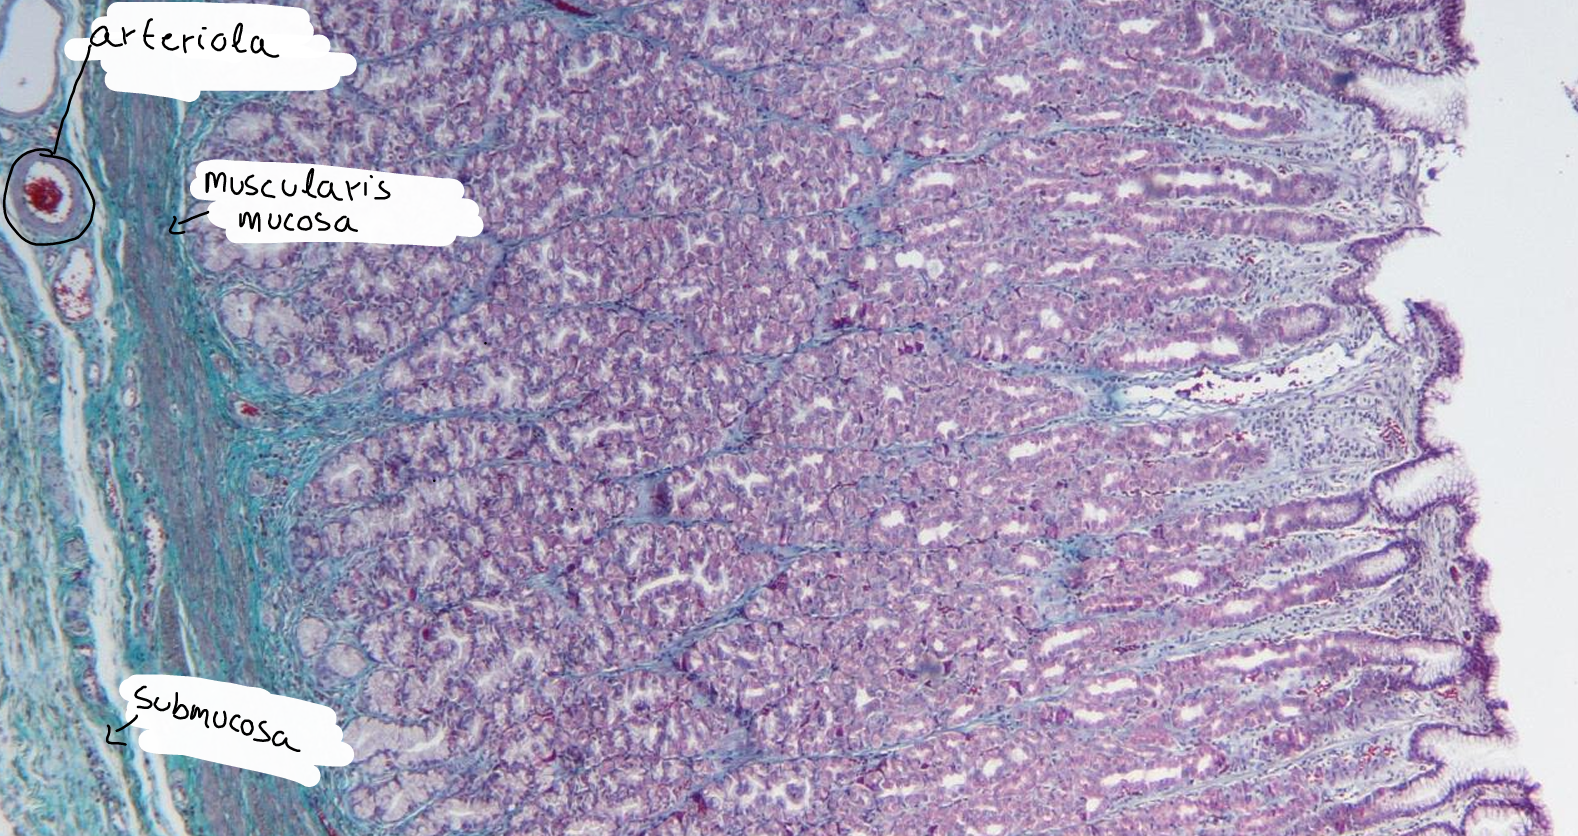

intestino grueso es la parte final del sistema digestivo, encargada de absorber agua y electrolitos, además de formar y eliminar las heces.

intestino grueso

colon